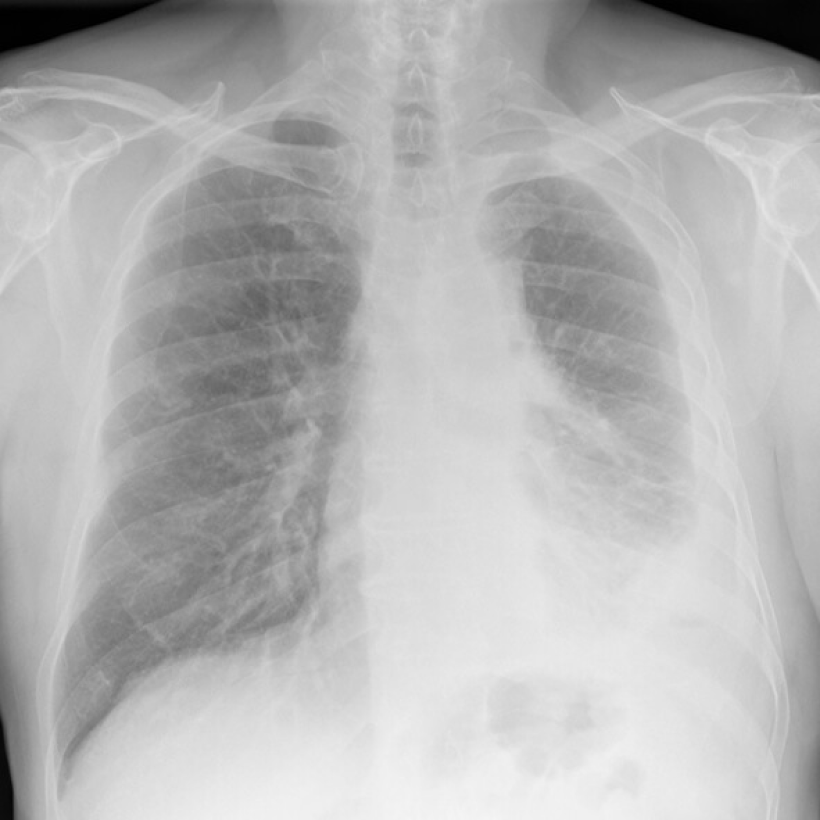

What Does Mesothelioma Look Like on an X-Ray?

Digital chest x-ray of advanced malignant mesothelioma on left.

On a chest X-ray, pleural or pericardial mesothelioma tumors appear as wispy white areas around the lungs, while calcified tumors appear bright white. Bones appear white and healthy lungs are dark. Most abnormalities appear as lighter areas that are hazy or solid.

Tumors and scarring may distort chest anatomy. Compressed lungs or a raised diaphragm can be visible on an X-ray.

X-rays are 2D, making it hard to determine if a tumor is in the lung, pleura or the mediastinum around the heart. Additionally, X-rays don’t clearly show peritoneal or testicular mesothelioma. CT, MRI and PET/CT scans offer more detailed images for all mesothelioma types.